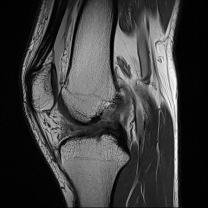

A torn ACL can be diagnosed by an orthopaedic specialist through: